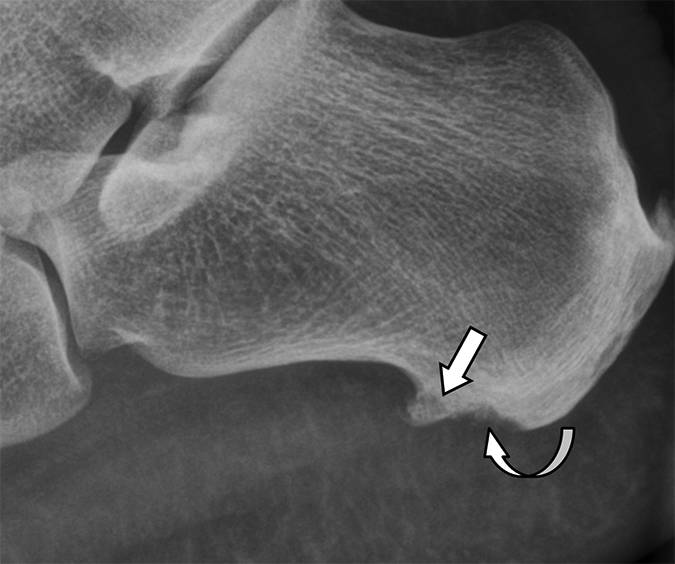

图3 -患者59岁,1型跟骨骨折,症状急性后足跟疼痛。 侧面放射照片显示优越位移的骨片(弯曲的箭头)和跟部结节的上部方面的供体位点缺陷(直箭头)。